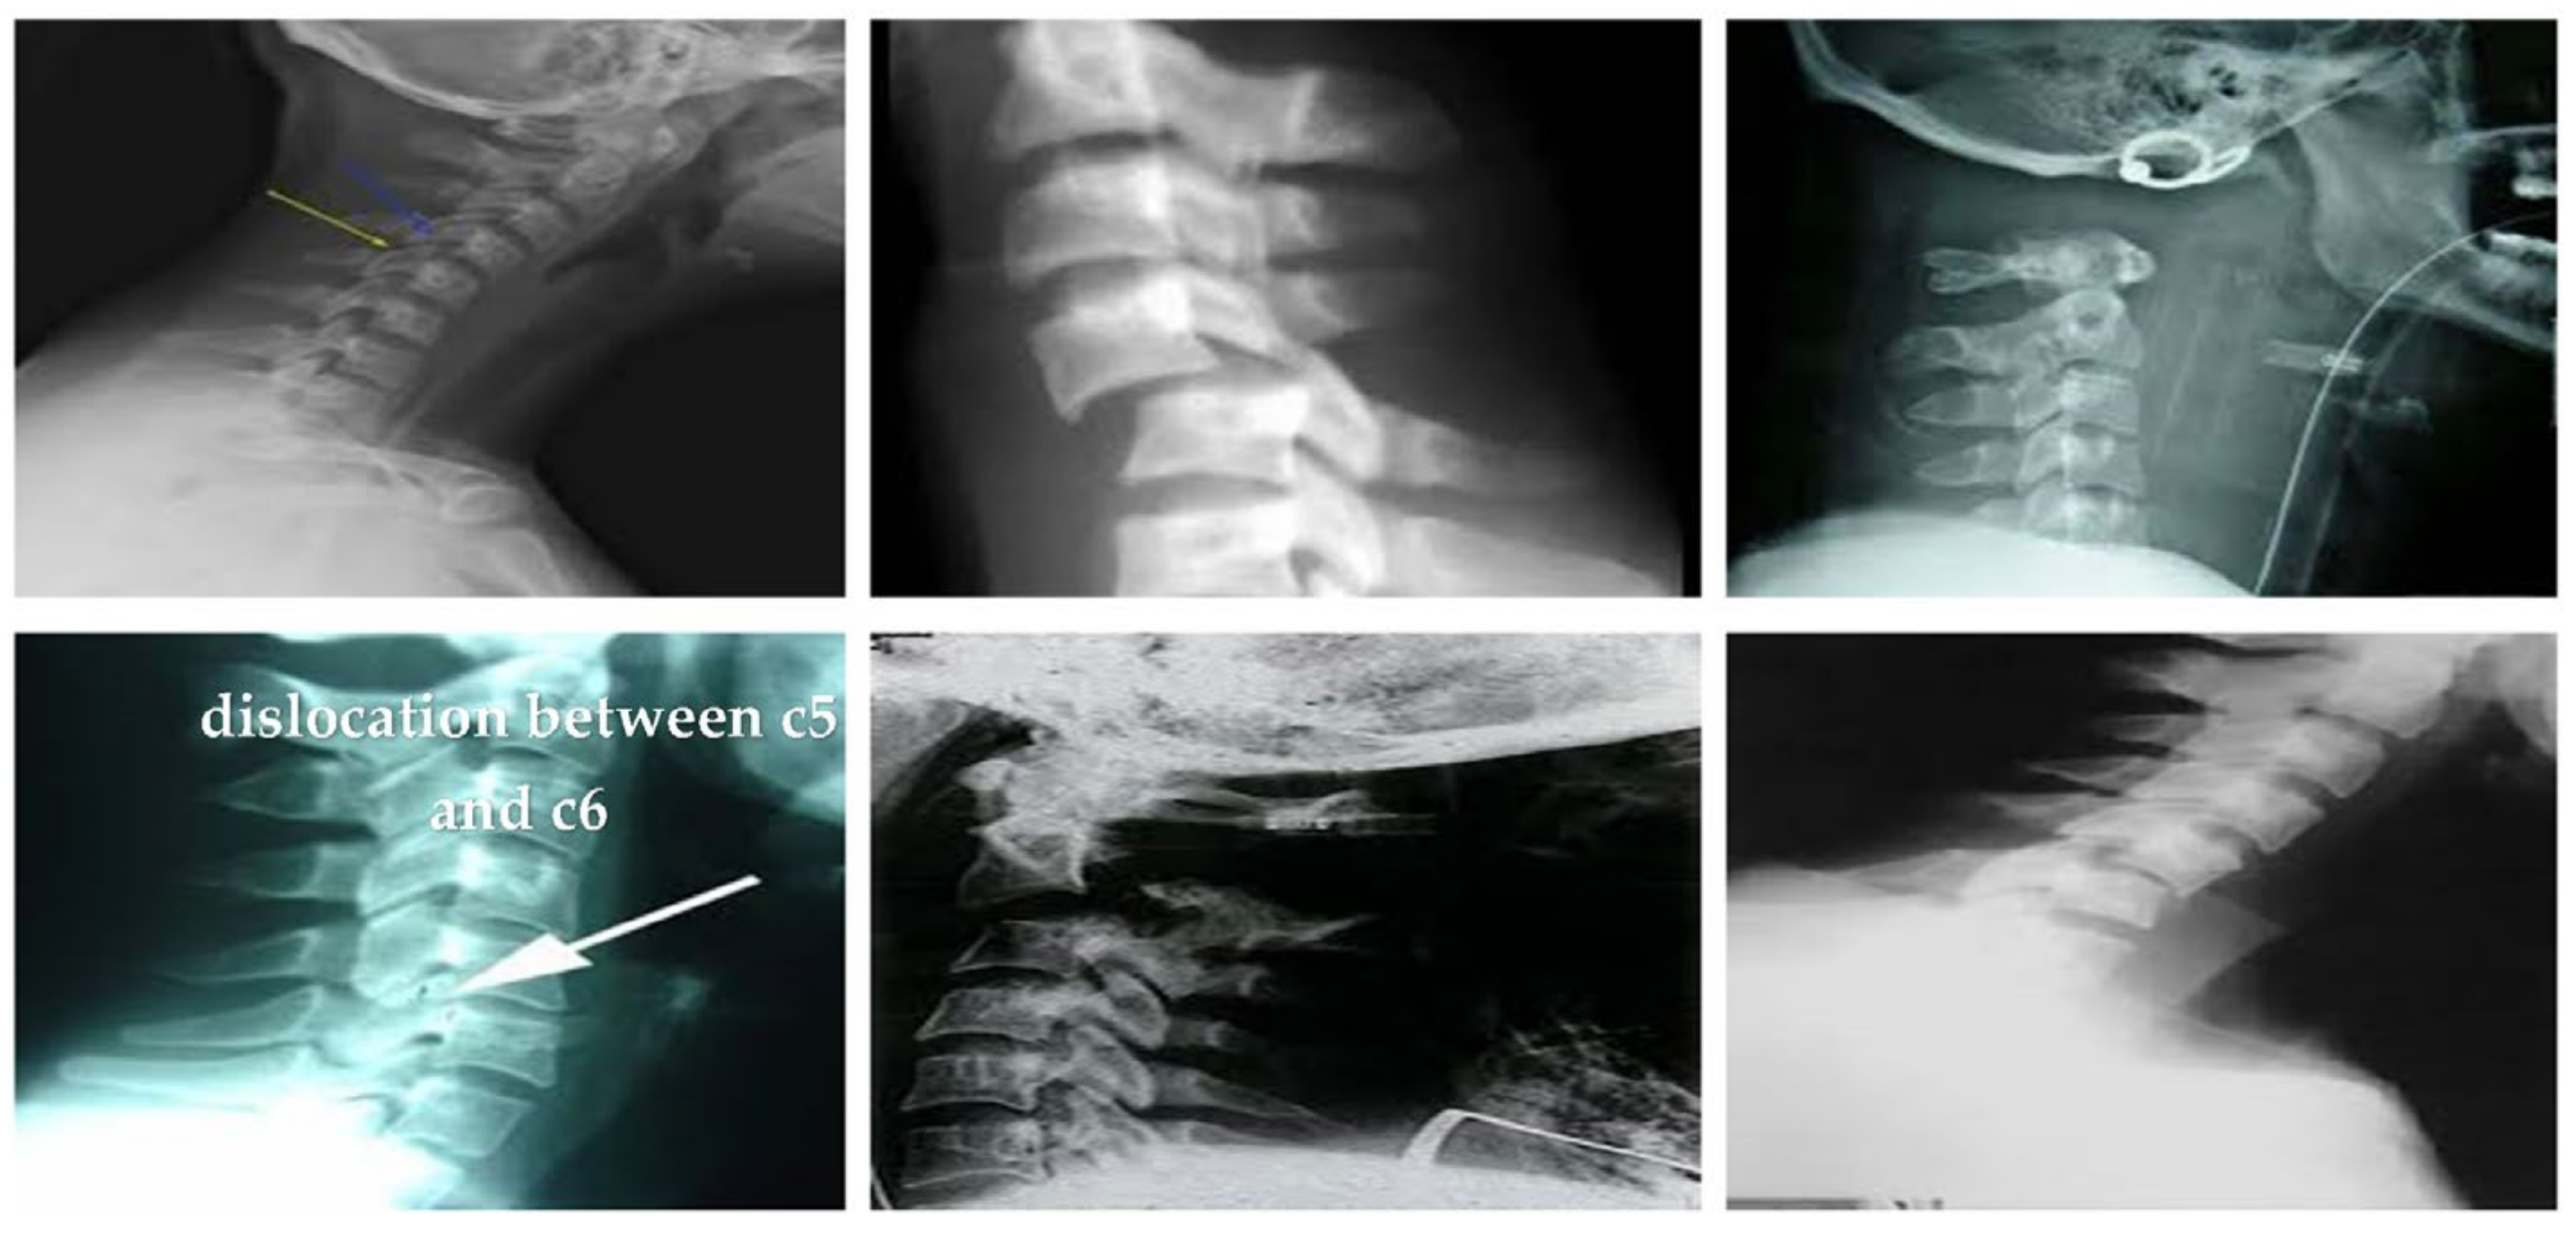

3.1. Datasets

4.1. Results and Discussion

4.1.2. Clinical Case Study